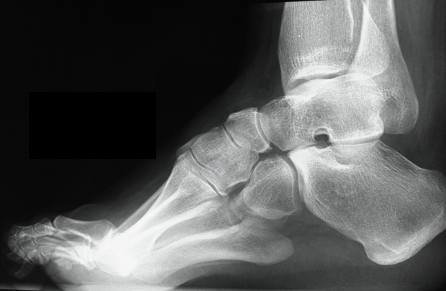

X-ray

Meary's angle

- longitudinal talus axis - 1st metatarsal angle

- normal 0o

- cavus > 20o

Calcaneal Pitch

- normal 20o or less

- > 30o abnormal